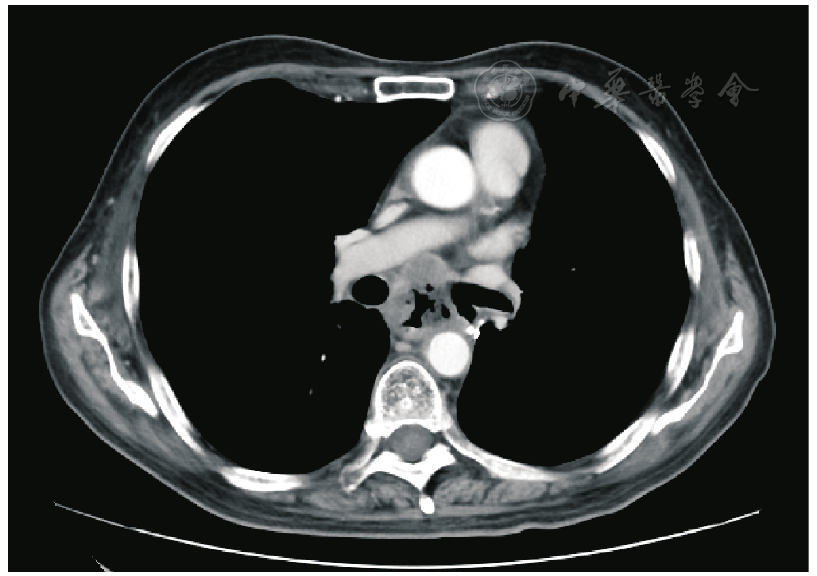

图1 胸部CT可见纵膈淋巴结肿大,与食管病变分界不清

图2 胸部CT示食管最狭窄段起始处